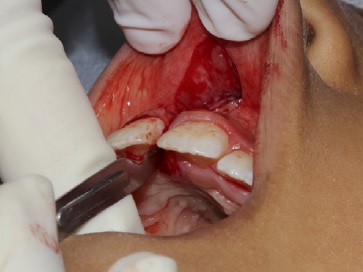

Paciente de oito anos de idade, sexo feminino, procuro a Clínica Integrada do Curso de Odontologia do Centro Universitário Ages (UniAges) juntamente com seu responsável para consulta dentária. Durante a anamnese e o exame clínico, foi observada a presença de freio labial superior fibroso que produzia isquemia ao ser tracionado e espaço interincisal (Figura 1), além de histórico hereditário paterno de diastema. Foi realizada radiografia periapical da região para avaliação dos dentes e das estruturas de suporte. A paciente estava na fase de dentição mista com a presença dos incisivos centrais e laterais superiores permanentes; com ausência dos caninos permanentes, ainda em processo de erupção dentária, não apresentava inflamação gengival, controle satisfatório de biofilme (menor que 20%) nem alteração sistémica. Assim sendo, diante da avaliação foi sugerido a cirurgia de frenectomia do freio labial superior.